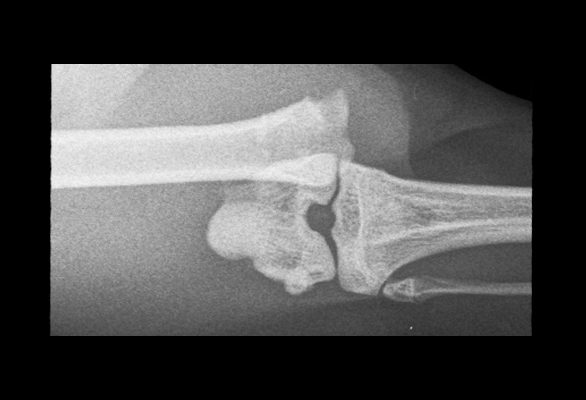

A full understanding of the injury is needed before a decision can be made on how best to manage it. This information is gathered by taking radiographs or by performing a CT scan.

Dislocated joints will need to be realigned, and this may be performed by careful manipulation or by surgery. The joint will then need to be maintained in this position whilst the local tissues repair.

Surgery aims to realign and stabilise the fractured bones to allow uneventful healing. There are numerous methods used to stabilise the fractured bone including the use of plates, screws, pins, and wire. These are hidden from view and placed under the skin (internal fixation).